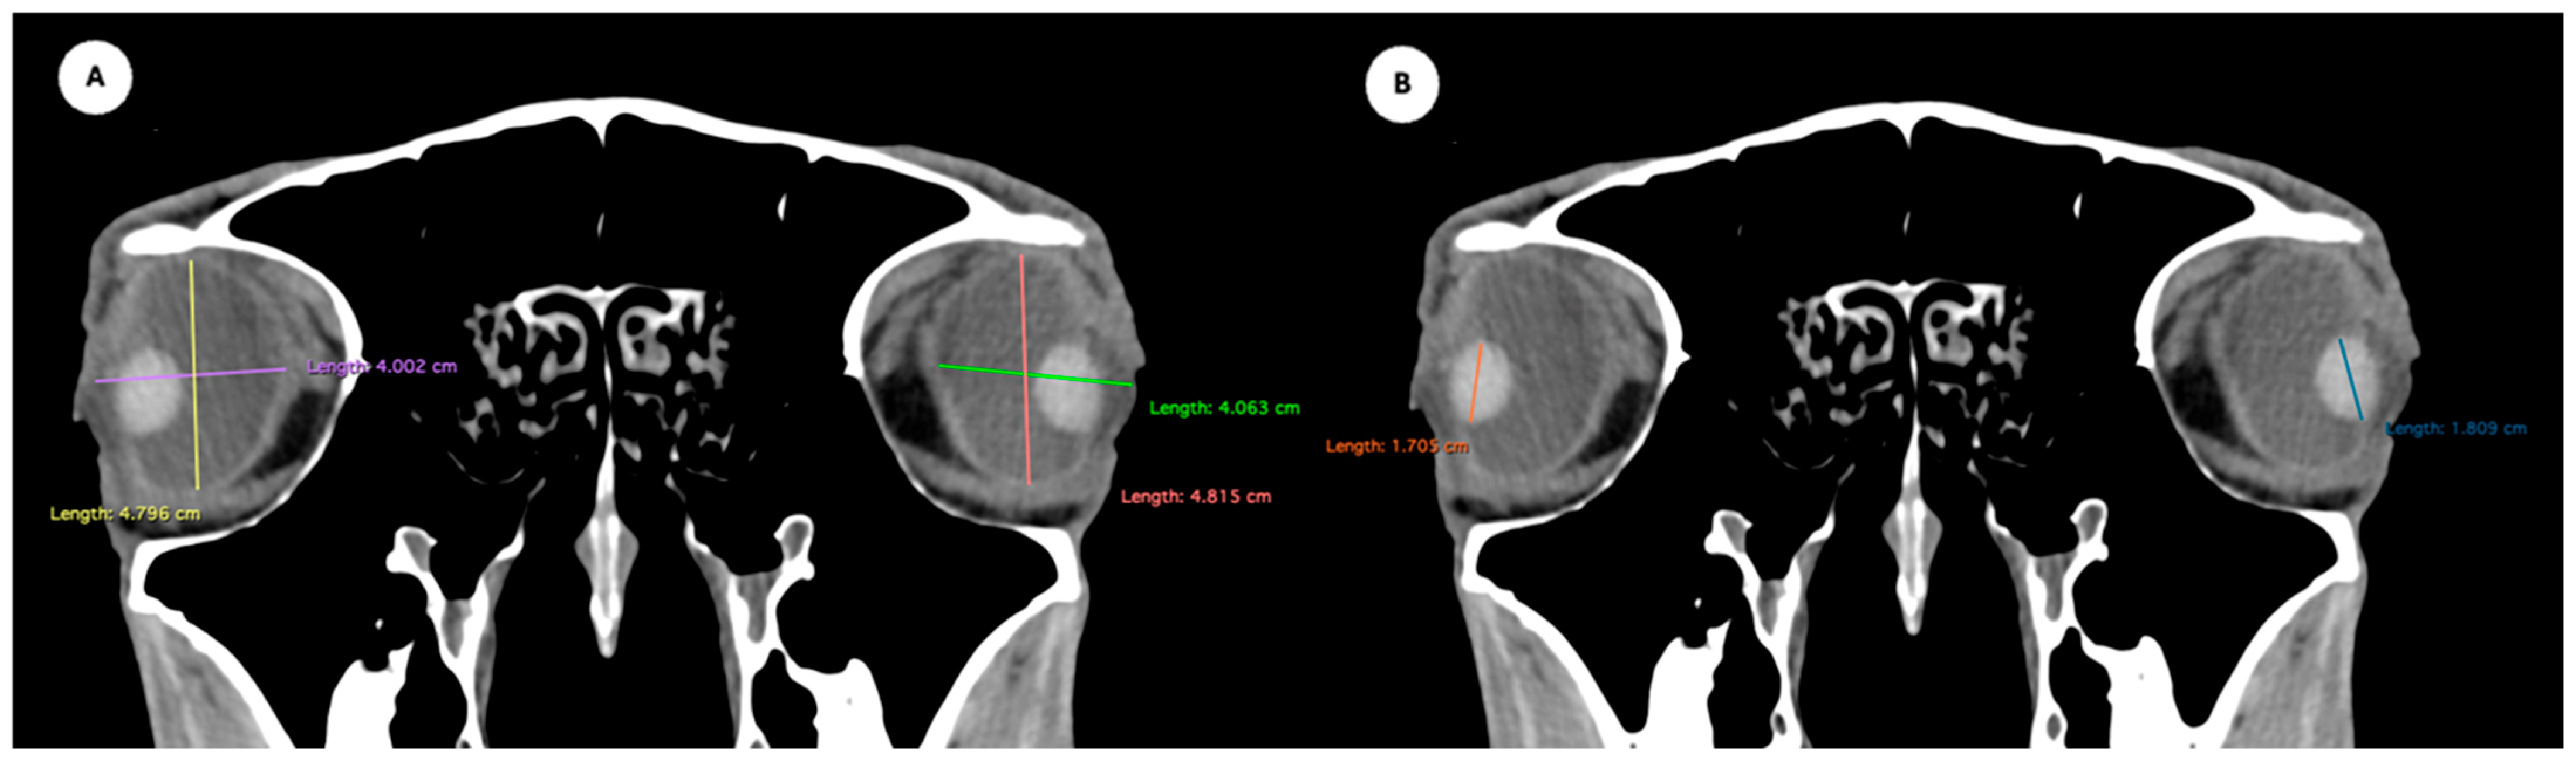

Figure 2. Dorsal multiplanar reconstruction (MPR) images showing (A) the maximal latero-medial distance of the lens and (B) the maximal latero-medial distance of the eyeball, measured perpendicular to the axial length, immediately caudal to the lens. - Orbital cavity height: Maximal dorsoventral distance of the orbital cavity at the level of the eyeball.

- Eyeball equatorial width and height: Maximal anterior–posterior distance (Figure 1A) and maximal lateromedial distance of the eyeball, measured perpendicular to the axial length (Figure 2B).

Table 1 provides summary statistics (mean, median, range, and standard deviation) for the internal ocular measurements of the left eye, right eye, and both eyes combined across all 20 horses. The average ocular measurements indicated that the eyeball height (5.19 ± 0.13 cm) was greater than its width (4.28 ± 0.12 cm), confirming the characteristic oval shape of the equine eye. The mean axial length was 5.09 ± 0.17 cm, consistent with previous descriptions of large-globe morphology in horses. The orbital cavity measured 5.27 ± 0.12 cm in height and 6.29 ± 0.14 cm in length. The anterior and posterior chambers had mean widths of 0.56 ± 0.07 cm and 2.26 ± 0.09 cm, respectively. The lens exhibited a mean height of 1.53 ± 0.06 cm, width of 1.23 ± 0.06 cm, and length of 1.63 ± 0.04 cm. These results collectively reflect the regular proportions and bilateral symmetry of the equine eyeball and its internal structures, as detailed in Table 1. The Mann–Whitney U test revealed no statistically significant differences in the measurements between the right and left eyes. Similarly, when all variables were considered collectively, the analysis confirmed the absence of significant differences between both eyes

All eyeball measurements were intercorrelated. Weak correlations were observed between length and width (ρ = 0.329; p = 0.033) and between length and height (ρ = 0.371; p = 0.015). A strong correlation was found between width and height (ρ = 0.704; p < 0.001). Orbital cavity height and length were significantly correlated (ρ = 0.639; p < 0.001), indicating a strong association. Orbital cavity height also showed significant correlations with all eyeball measurements: width (ρ = 0.360; p = 0.019), height (ρ = 0.419; p = 0.006), and length (ρ = 0.542; p < 0.001). In contrast, orbital cavity length was only correlated with eyeball length (ρ = 0.422; p = 0.005). Lens dimensions showed varying degrees of correlation. A strong correlation was found between lens height and lens width (ρ = 0.788; p < 0.001), while a weak correlation was observed between lens height and lens length (ρ = 0.306; p = 0.048). No significant correlation was found between lens width and lens length (ρ = 0.279; p = 0.074). Lens width demonstrated moderate-to-weak correlations with several eyeball and orbital cavity measurements: eyeball width (ρ = 0.346; p = 0.025), eyeball height (ρ = 0.332; p = 0.032), eyeball length (ρ = 0.523; p < 0.001), orbital cavity height (ρ = 0.349; p = 0.023), and orbital cavity length (ρ = 0.484; p = 0.001). Lens height showed moderate correlations with eyeball length (ρ = 0.538; p < 0.001), orbital cavity height (ρ = 0.435; p = 0.004), and orbital cavity length (ρ = 0.539; p < 0.001). Conversely, lens length was not significantly correlated with any eyeball or orbital cavity measurements. Finally, the widths of the posterior and anterior chambers were moderately correlated (ρ = 0.580; p < 0.001). Both variables showed weak to moderate correlations with all eyeball, orbital cavity, and lens dimensions (ρ = 0.337–0.650; p = 0.029 to <0.001), except for the posterior chamber width with eyeball length (ρ = 0.232; p = 0.140), and the anterior chamber width with lens length (ρ = 0.204; p = 0.195), which were not statistically significant.